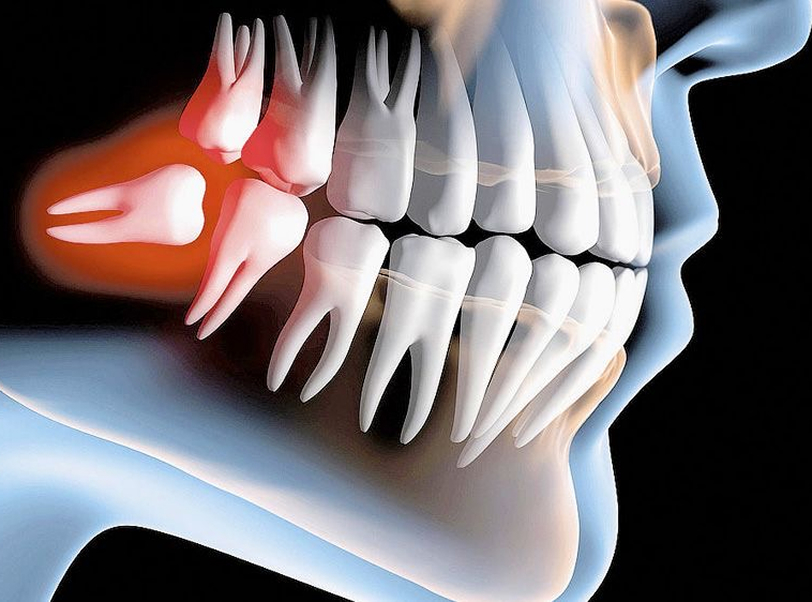

Realizamos a remoção de dentes inclusos, impactados ou mal posicionados, com técnicas minimamente invasivas que reduzem dor, edema e tempo de recuperação. Ideal para prevenção de infecções, desalinhamentos e complicações futuras.

Cirurgias auxiliares ao tratamento ortodôntico, como extrações de terceiros molares, caninos inclusos, tracionamento dentário e remoção de obstáculos ósseos. Atuação conjunta aos ortodontistas para acelerar e potencializar os resultados do alinhamento dentário.